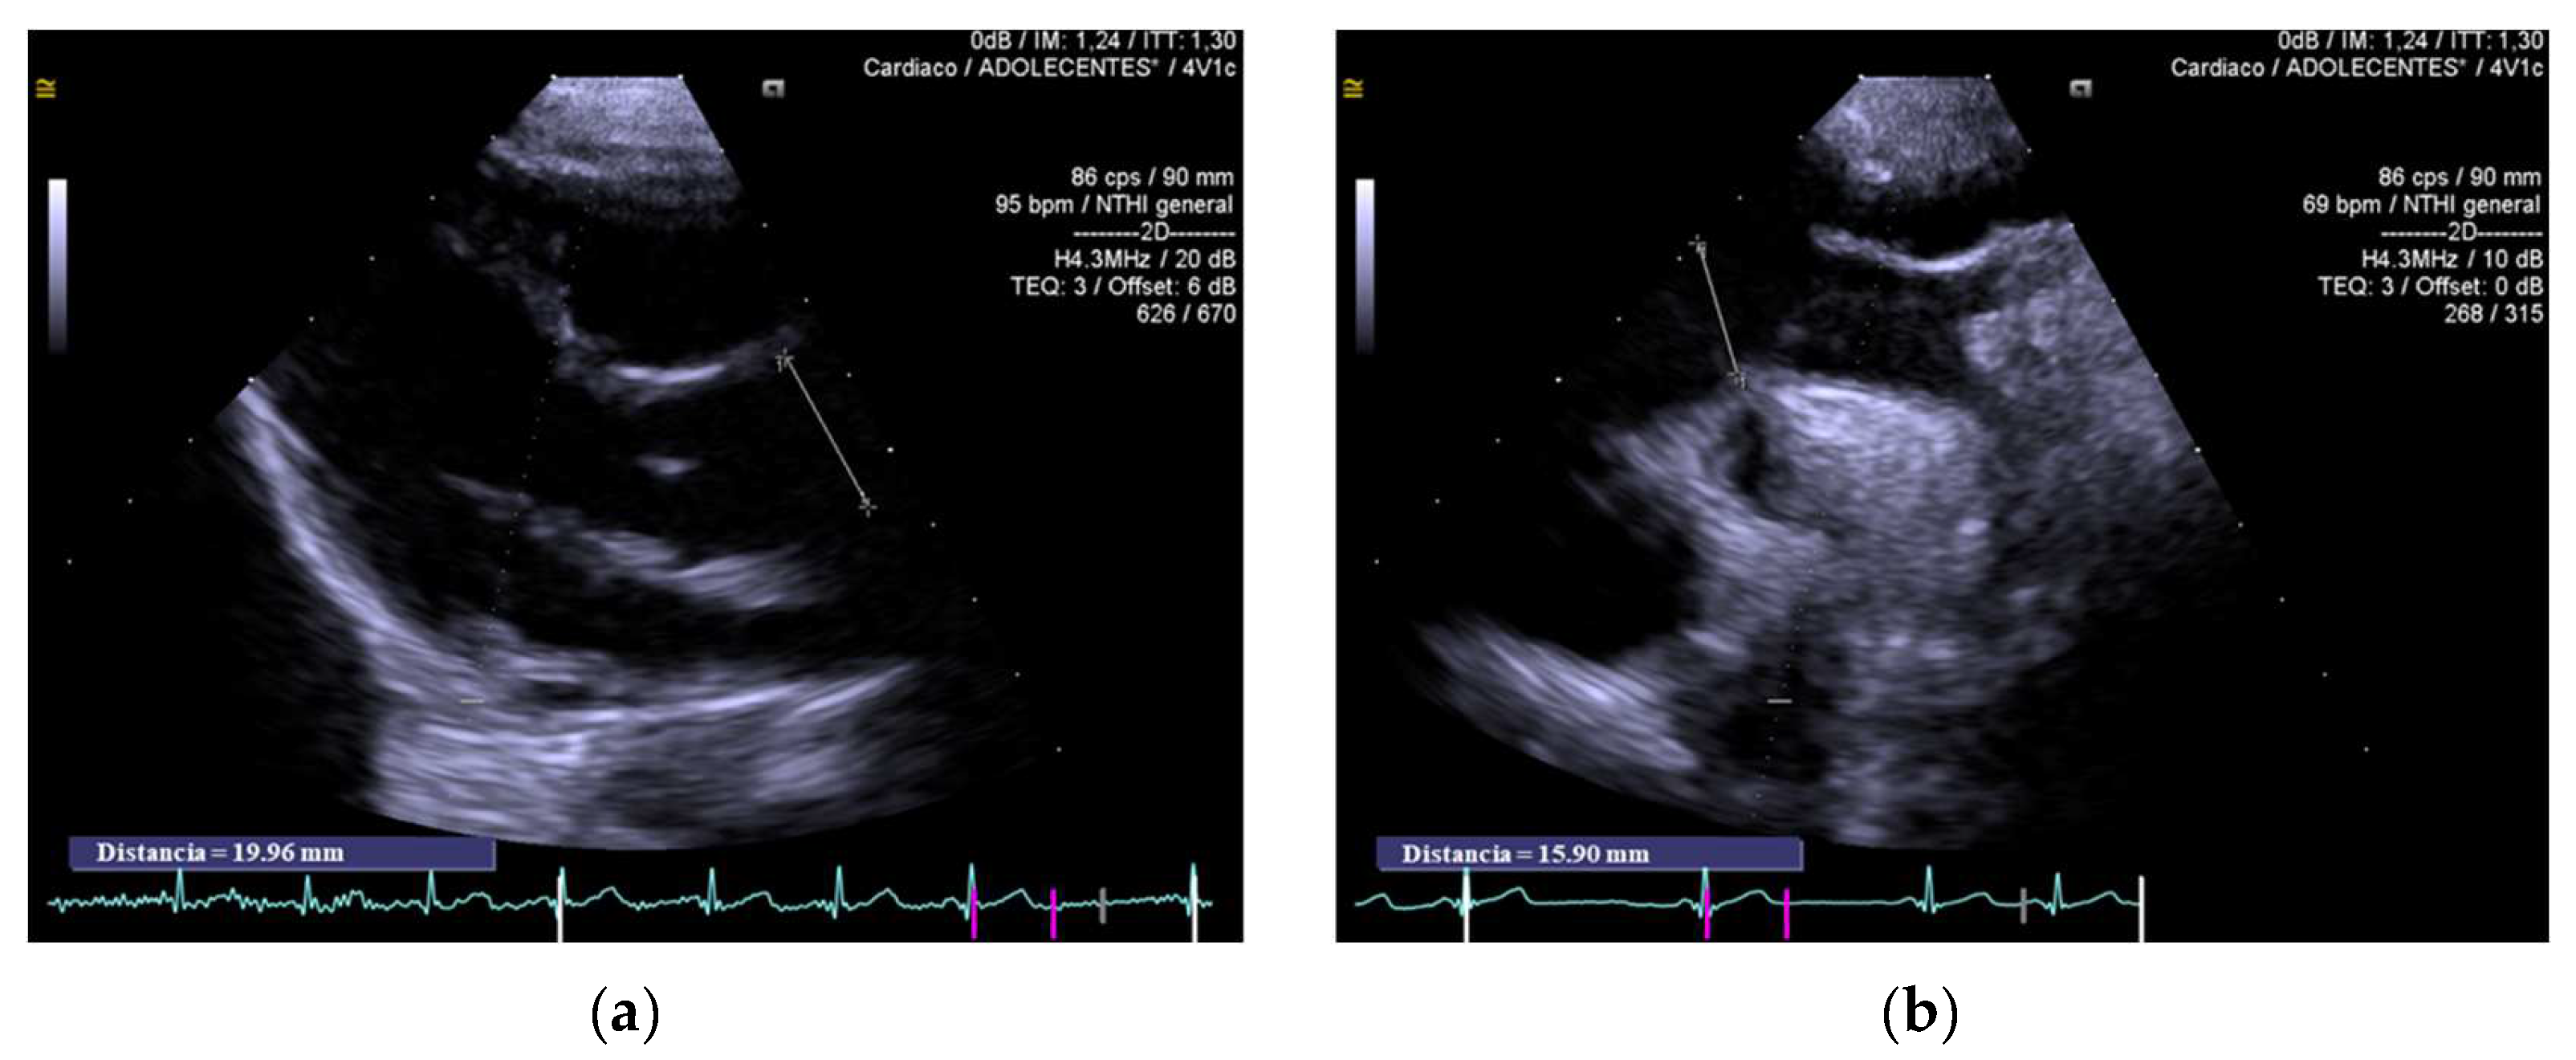

3.2. Echocardiographic Findings and Speckle-Tracking-Echocardiographic Parameters